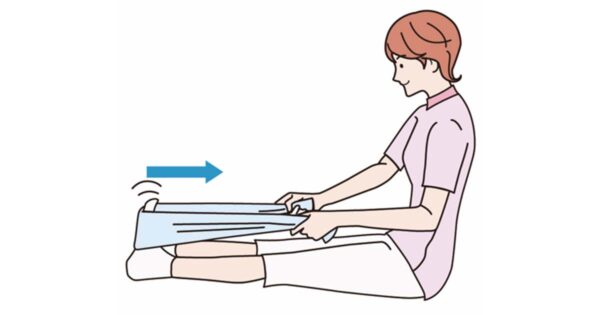

5. リハビリや運動に対するモチベーションを与える

リハビリ計画を遵守することが重要です。多くの人にとって、これは 1 日に 2 ~ 3 回 30 分間歩くことを意味します。医師は、1 日に 2 ~ 3 回、さらに 20 ~ 30 分間の運動を推奨することもあります。

歩いたり運動したりすると痛みを感じることがあります。これは正常です。患者がリハビリ計画を中止したいという意思を表明した場合は、彼らが感じていることはよくあること、リハビリが回復を早めるのに役立つことを思い出させてください。

自分の努力、結果、進捗状況をグラフ化できるようにすると、モチベーションを維持できる可能性があります。子どもたちと一緒に運動したり歩いたりすることも、子どもたちが順調に進むのに役立つかもしれません。